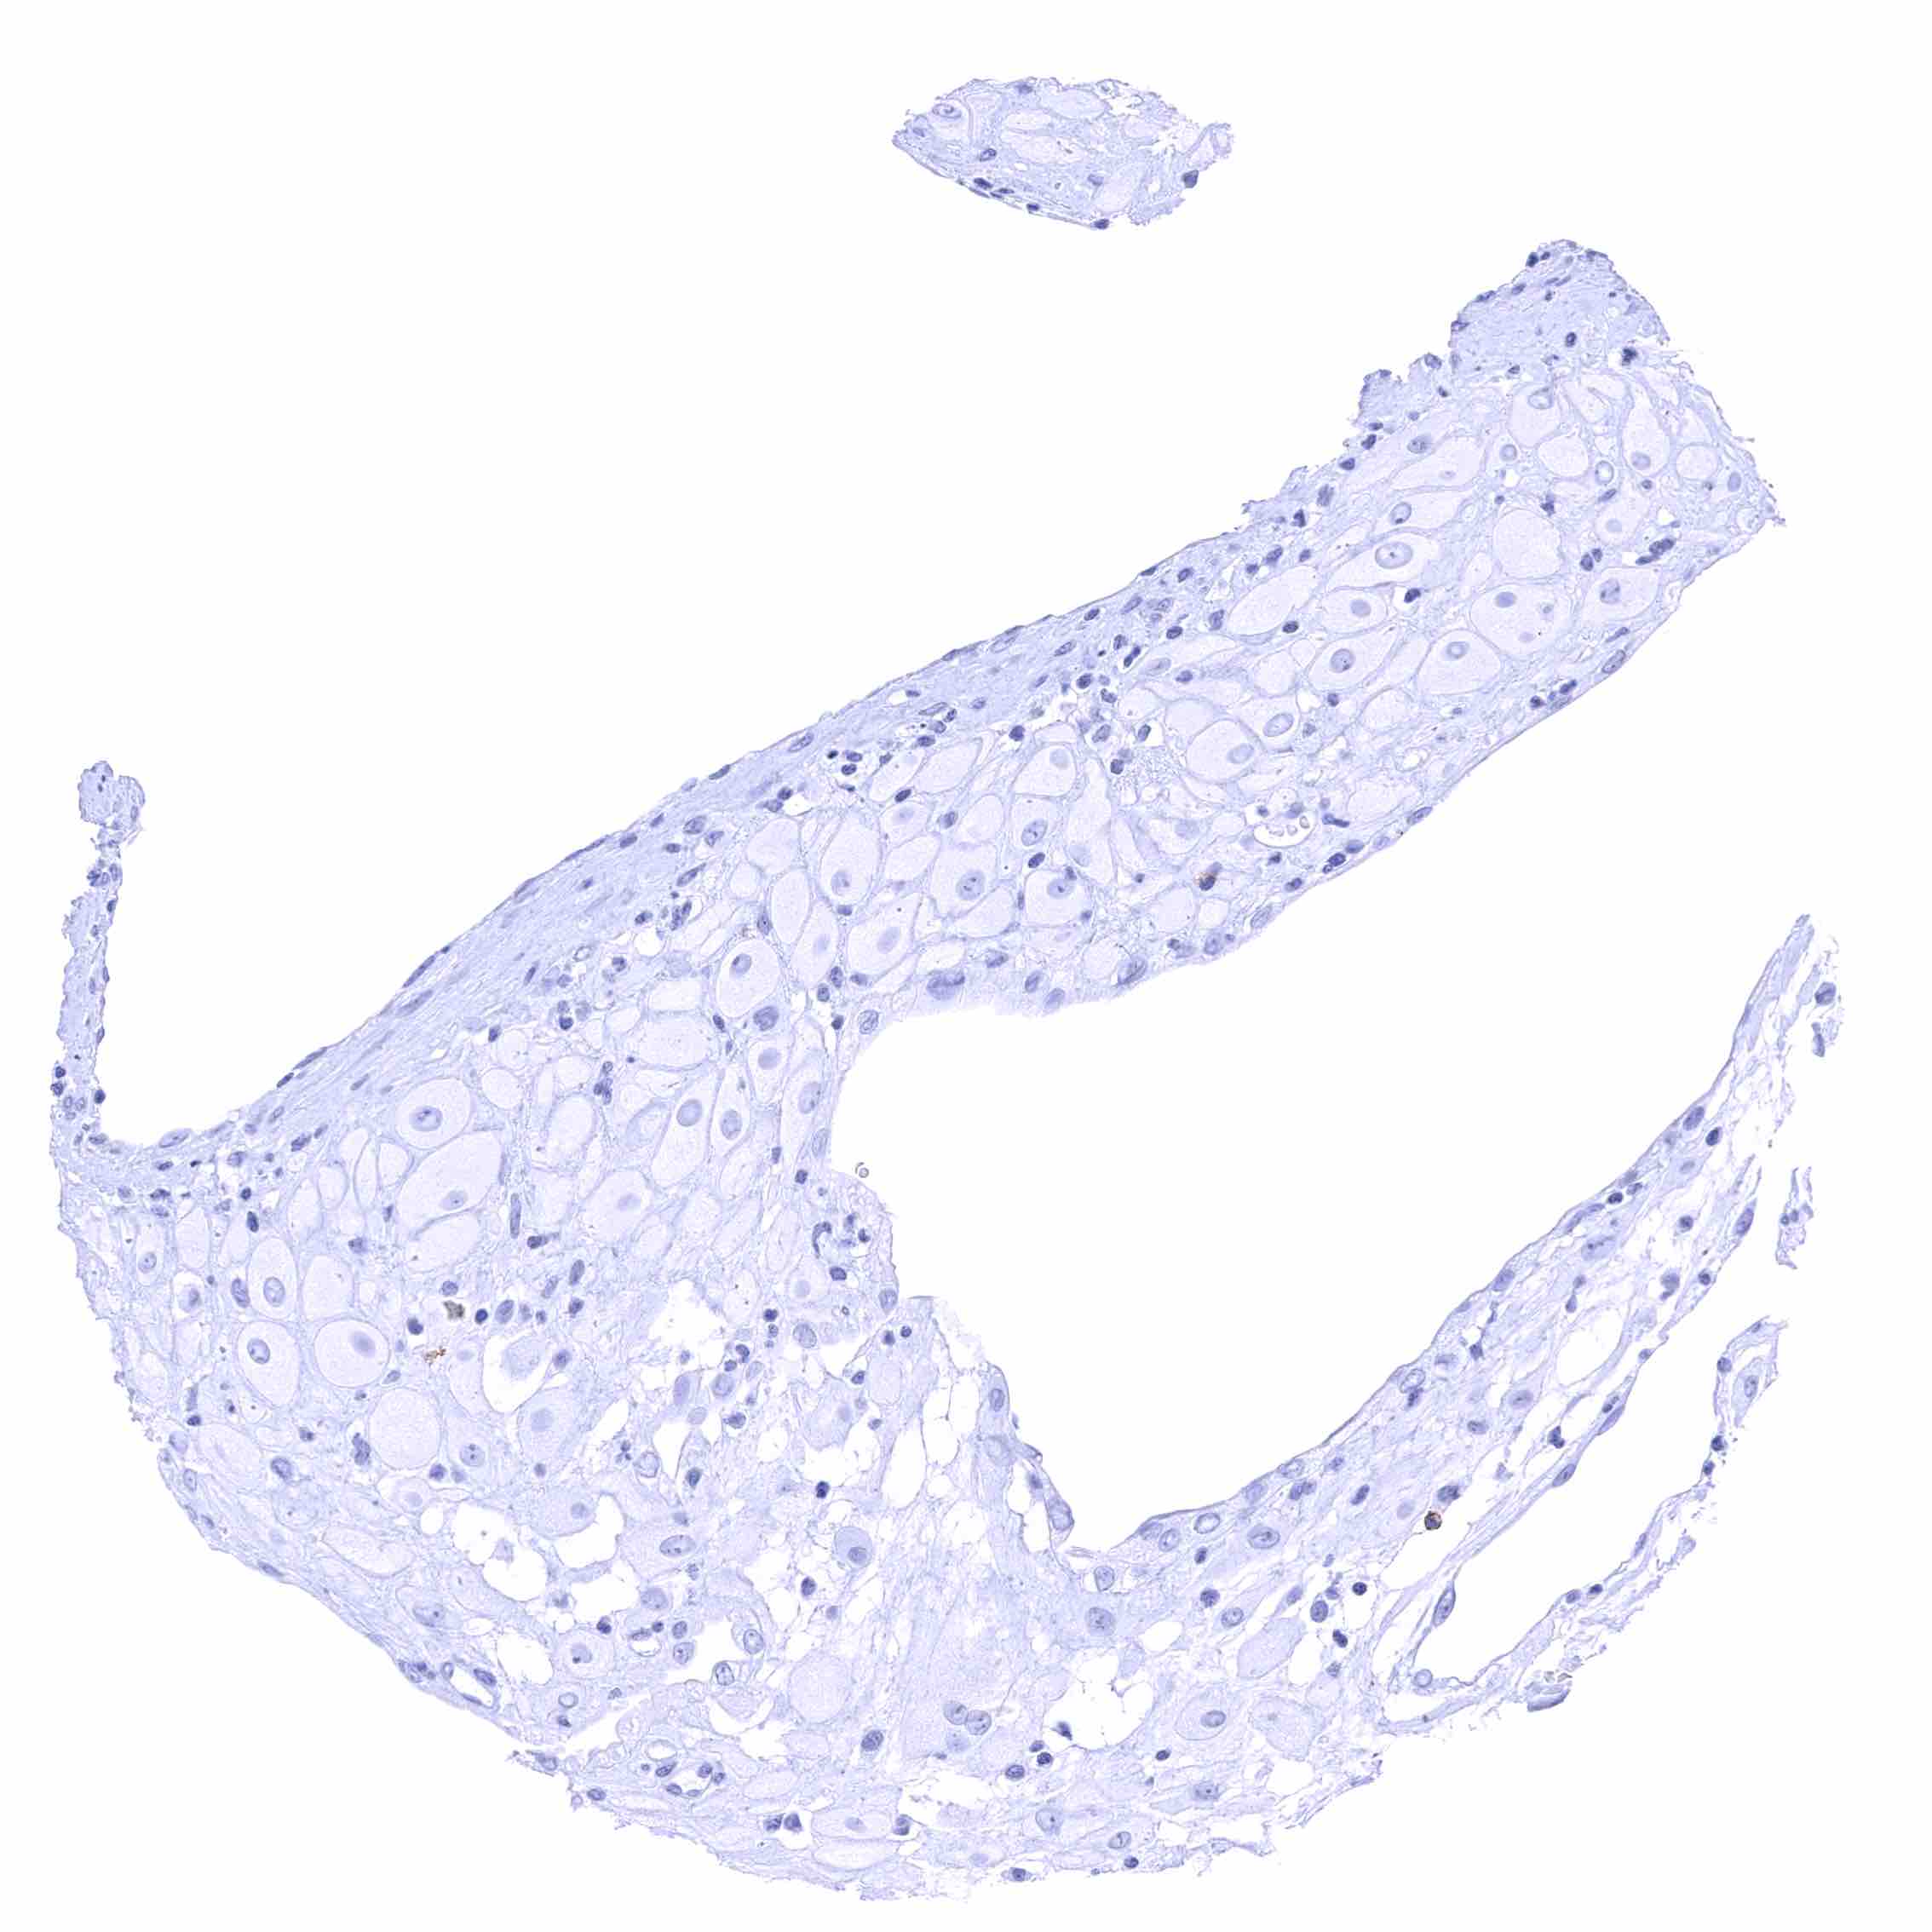

Urinary bladder, urothelium – Membranous CD70 staining of intraepithelial lymphocytes.